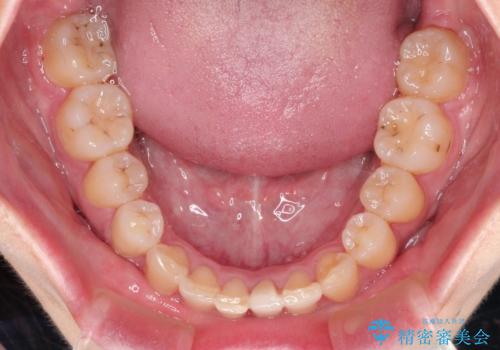

ハーフリンガル ワイヤー矯正による非抜歯・過蓋咬合の治療

- 非抜歯、大臼歯遠心移動による臼歯関係の是正・過蓋の改善をハーフリンガル・ワイヤー矯正にて計画した。